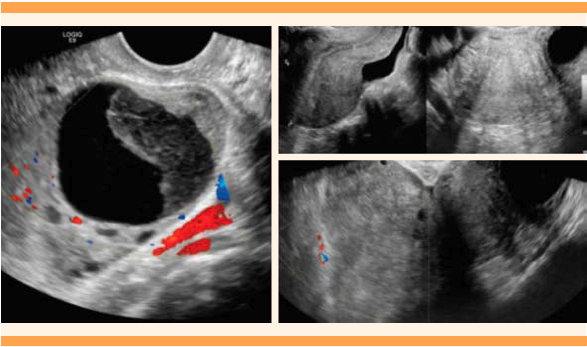

Los análisis paraclínicos no reportaron leucocitosis ni anemia, la función renal estaba preservada (creatinina 0.62 mg/dL, BUN 11). La ecografía transvaginal reportó: útero en anteversión de forma, tamaño y ecogenicidad normal, sin lesiones en el miometrio, de 57 x 54 x 45 mm, volumen de 74.7 cc. El cuello del útero reportó un aspecto ecográfico normal. El espesor ecogénico del endometrio fue de 6.1 mm. El ovario izquierdo se encontró aumentado de tamaño: 54 x 53 x 41 mm, con 61.67 cc de volumen. En su interior se identificó una lesión redonda, hipoecoica, con componente sólido en su interior y aspecto en vidrio esmerilado, sin flujo de Doppler color de 38 x 36 x 36 mm. No fue posible visualizar el ovario derecho, en su topografía se encontró una gran masa, evaluada de manera incompleta por vía transvaginal, con componente sólido y quístico, sin flujo al Doppler color, sin claro plano de clivaje con la pared del útero de dimensiones aproximadas de 174 x 154 x 106 mm y 1494 cc de volumen líquido libre, particulado, en la pelvis. Figura 1

Figura 1 Imágenes ecográficas de lesiones anexiales. La imagen del lado izquierdo corresponde al anexo, con Doppler color. La imagen del lado derecho es la visualización ecográfica del útero en corte longitudinal y porciones de masa anexial derecha, con Doppler color.